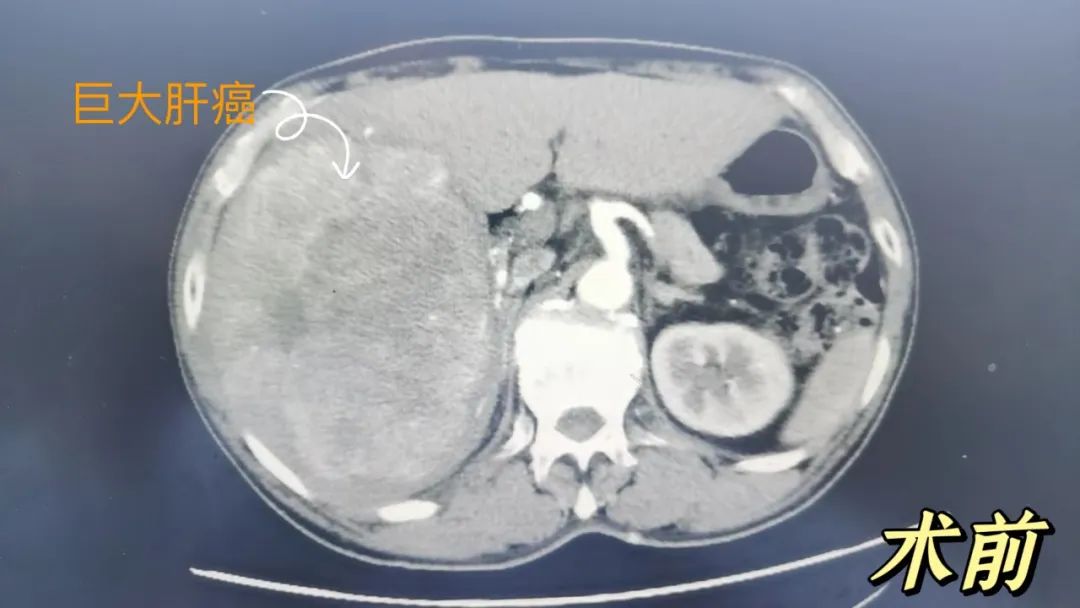

时间回到 2023 年 5 月,63 岁的农民王大伯因「乏力一月」去医院检查,竟然查出:肝脏占位,考虑巨大肝癌;腹腔积液。AFP>20000.0ng/ml。

王大伯找到句容市人民医院普外科陈祥主任医师。这么大的肿瘤确实罕见,在仔细阅读 CT 片后,陈祥给王大伯吃了「定心丸」:王大伯肝功能 Child 分级

(肝硬化患者肝脏储备功能进行量化评估的分级标准 )B 级,未见明显肝硬化。目前肝右叶占位性病变考虑原发性肝癌,虽病灶巨大,但未见侵犯腔静脉、门静脉未见明显癌栓,可以手术切除。

术中探查:肝右叶明显肿物,大小约 18×15×15 cm,足足一个小南瓜般!